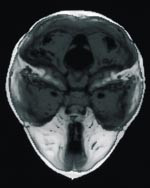

Prematur metopicasynostose gir ikke redusert intrakranialt volum totalt (35), men fremre skallegrop er ofte liten og ledsaget av kompensatorisk økt midtre skallegrop (13).

Enkle kraniosynostoser kan av og til være ledsaget av forhøyet intrakranialt trykk. Ved cerebral CT finner man økt mengde ekstracerebral væske bifrontalt hos 14 % (9). Hos barn med enkle ensuturs synostoser har man funnet forhøyet intrakranialt trykk hos 9 – 17 % av pasientene, mens det hos ytterligere 27 – 38 % var i grenseområdet (6 – 8). I en studie av 12 barn med enkle metopicasynostoser, fant Thompson og medarbeidere (8) forhøyet intrakranialt trykk hos fire, mens ytterligere fem var i grenseområdet. Imidlertid påviser man behandlingstrengende hydrocephalus hos kun 4 % ved enkle metopicasynostoser (9, 19).

Corpus callosum-dysgenesi er den hyppigst forekommende ledsagende intracerebrale anomali ved enkle metopicasynostoser, og finnes hos omkring 4 % (9, 25, 37).